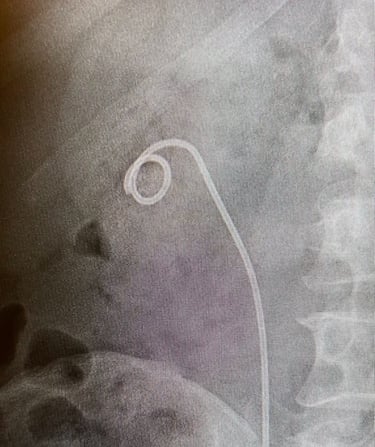

5. Stent Yerleştirme: Üreterin iyileşmesine yardımcı olmak ve idrar akışını sağlamak için işlem sonunda üreteral stent (Double-J stent) yerleştirilebilir.

Fleksible URS + j stent takılması